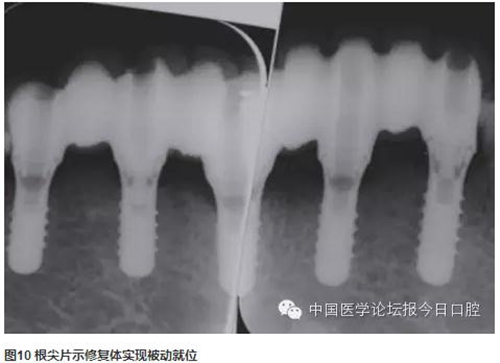

技工室制作純鈦支架,聚合瓷修復(fù)牙齒和牙齦形態(tài),患者口內(nèi)試戴,只將一個種植體的固定螺絲加力,拍片可見其余3顆種植體均實現(xiàn)被動就位,然后將4顆種植體固定螺絲加力,封口(圖2~圖10)。

曲面體層片示:種植體基臺與修復(fù)體密合性良好。1年后復(fù)診,支架無松動、折斷,中央螺絲未見折斷、松動,修復(fù)體未見崩瓷。種植體無松動,種植體周圍少量軟垢存,黏膜未見紅腫。種植體周圍探診深度:下頜左側(cè)尖牙(近中2mm、頰側(cè)3mm、遠(yuǎn)中4mm、舌側(cè)2mm),下頜左側(cè)中切牙(近中2mm、頰側(cè)2mm、遠(yuǎn)中4mm、舌側(cè)2mm),下頜右側(cè)側(cè)切牙(近中2mm、頰側(cè)2mm、遠(yuǎn)中3mm、舌側(cè)3mm),下頜右側(cè)第一前磨牙(近中3mm、頰側(cè)2mm、遠(yuǎn)中4mm、舌側(cè)3mm)(圖11~圖13)。